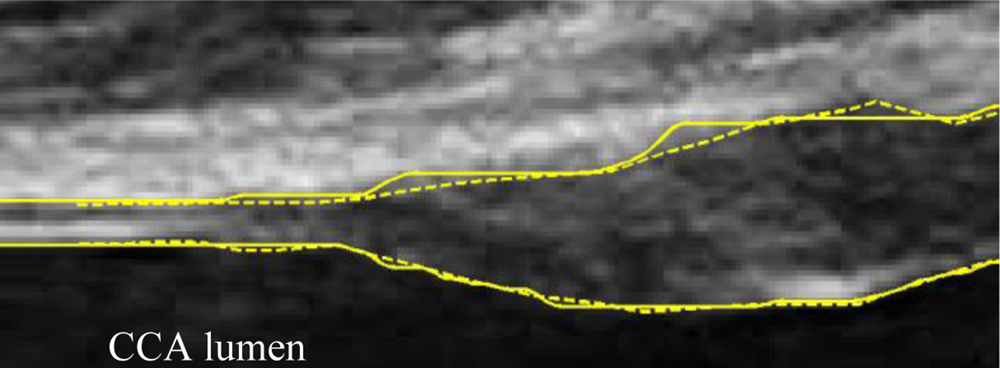

A typical B-mode image is shown in Figure 1. There are plaques on both near and far walls. On the contrary, a typical CCA image without plaque having thin and thick IMT is shown in Figures 2 and 3, respectively. Outlining the boundaries of intima and adventitia is not easy, especially on the near wall. Some features have been studied in previous studies [7,11], in which the most frequently used feature is the gradient of gray-values. From our previous studies [7,14,17], it is found that MacLeod operator combined with some specific enhancement filters are very suitable for feature extraction in intima and adventitia detections.

Figure 4 demonstrates the noise reduction effect of the enhancement filter. In cases without plaques, the thickness of sub-intima does not change on a large scale. If it has plaques, the noise layer existing in the sub-intima is not so strong and therefore, it can be ignored. The size of the filter is based on the consideration of the sensor’s frequency and the anatomic structure. Since the normal IMT is around 0.5 mm for young persons and the sensor is 10 MHz, therefore, the pixel size is about 0.1 mm and the IMT is around 5 pixels. That is the reason why the filter size is 7 × 7. Via this design, the IMT can be detected with less interference from the noise layer.

According to our experience the enhancement filter in (2) combined with MacLeod filter produces good results for the far wall IMT detection. However, it is not the case for the near wall. Figure 5 demonstrates one typical problem. This image is a sub-image extracted from a raw image in a sequence. Some noises existed under the intima when the artery is in the systolic cycle because its larger moving speed. This will cause ambiguity in IA detection because most of the rest images have no such kind of noises. We therefore propose a method to alleviate this problem.

The ambiguity results from the fact that the directional gradient of gray values cannot differentiate the interface between the lumen-intima interface and lumen-noise interface. If the gradient of the interface between the noise and artery lumen is larger than that between media and adventitia (Figure 5 shows the case), then the following DDP will have a faulty result. The problem then becomes how to enhance the interface between media and adventitia. We observed that there are large gray values under both lumen-intima and media-adventitia interfaces in the near wall. We can make good use of this information. Nevertheless, we do not hope to enhance the outer wall simultaneously, since it will result in ambiguity in searching the dual lines, i.e., the intima and the adventitia. To solve this problem we apply dynamic programming to find out the outer wall first. Then an additional feature image (H) is calculated as follows: